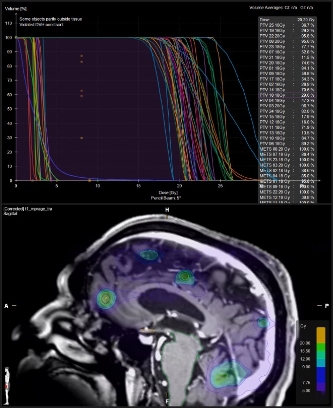

Previo a la primera sesión acudes a una cita para diseñar e individualizar tu tratamiento a través de la simulación y planeación. El objetivo de la simulación es determinar en un equipo de tomografía (TAC simulador) que será lo óptimo para las sesiones de tu curso terapéutico. En esta primera sesión podemos obtener imágenes de tomografía computada que proporcionan información detallada de la localización, el volumen, estructuras que rodean al tumor, etc. Todos estos datos se envían vía red al planificador de tratamiento cuyo software o programa de planeación reconstruye un modelo computacional de tu lesión o lesiones. Sobre este modelo virtual los físicos médicos y dosimetristas delimitan los volúmenes blancos y los órganos de riesgo (tejidos sanos circundantes), calculan las dosis precisas y las direcciones de los haces de radiación que se apuntarán al tumor, y junto con tu radio-oncólogo, definen el plan de tratamiento específico que será enviado al acelerador lineal sin capacidad de modificaciones y con control detallado.

Planeación virtual de tumor en pulmón. Físicos médicos y dosimetristas han delimitado los volúmenes blancos y los órganos de riesgo (tejidos sanos circundantes) y calculado la distribución de dosis precisas.

Planeación virtual de tumor en el hígado. Físicos médicos y dosimetristas han delimitado los volúmenes blancos y los órganos de riesgo (tejidos sanos circundantes) y calculado la distribución de dosis precisas, así como, las direcciones de los haces de radiación que se apuntarán al tumor.